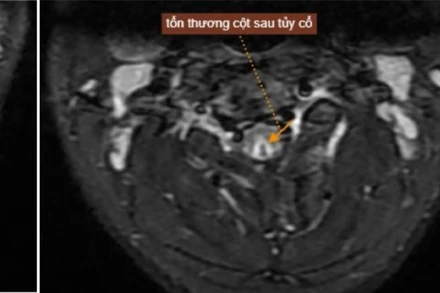

Sau khi hít khí N₂O trong bóng cười thường xuyên, nam thanh niên 20 tuổi nhập viện trong tình trạng tê bì, yếu chân tay, được chẩn đoán tổn thương tủy cổ.

Sau khi sử dụng bóng cười liên tục trong vòng 10 ngày, mỗi ngày khoảng 10 quả, nam bệnh nhân 15 tuổi nhập viện trong tình trạng tổn thương tủy cổ, tê yếu tay chân do ngộ độc khí N20.